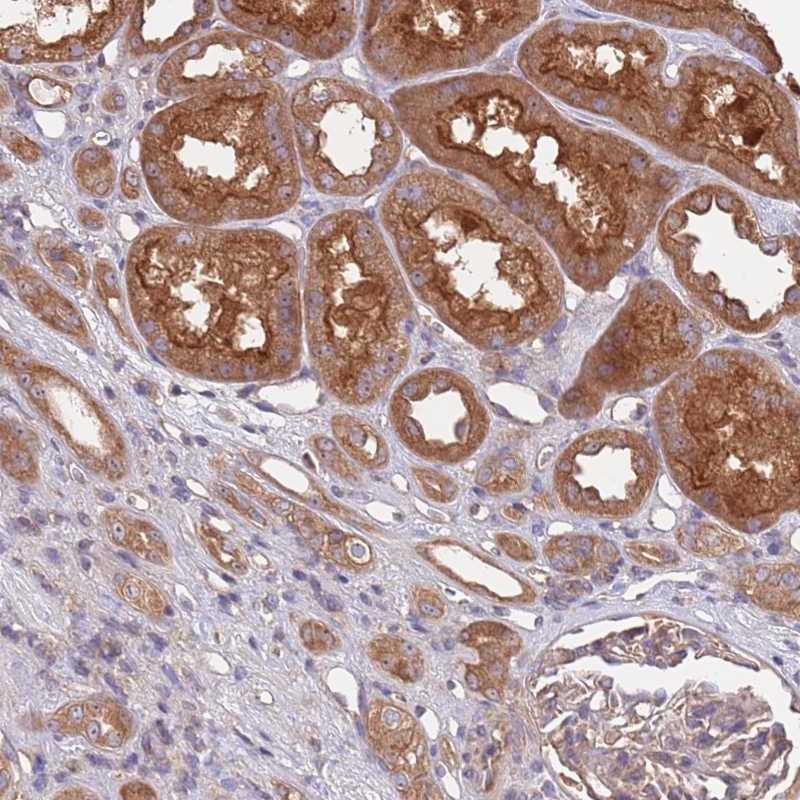

Immunohistochemical staining of human kidney shows strong cytoplasmic positivity in renal tubules.